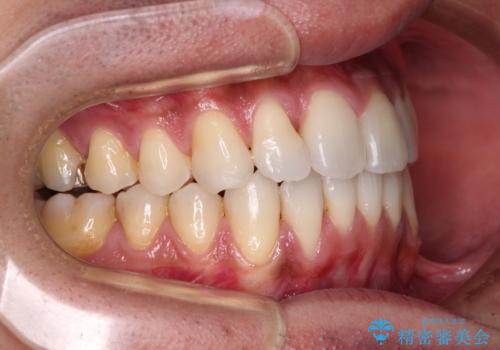

上顎の狭い歯列をインビザラインで拡大

- 上下前歯の叢生を気にして来院された患者様です。

奥歯はクロスバイトとなっているので上顎は側方拡大を行いつつ、上下全体の叢生をインビザラインにより改善することとしました。

治療途中でクリーニングやホワイトニングを行い、歯列が整うと同時に明るい口元となりました。